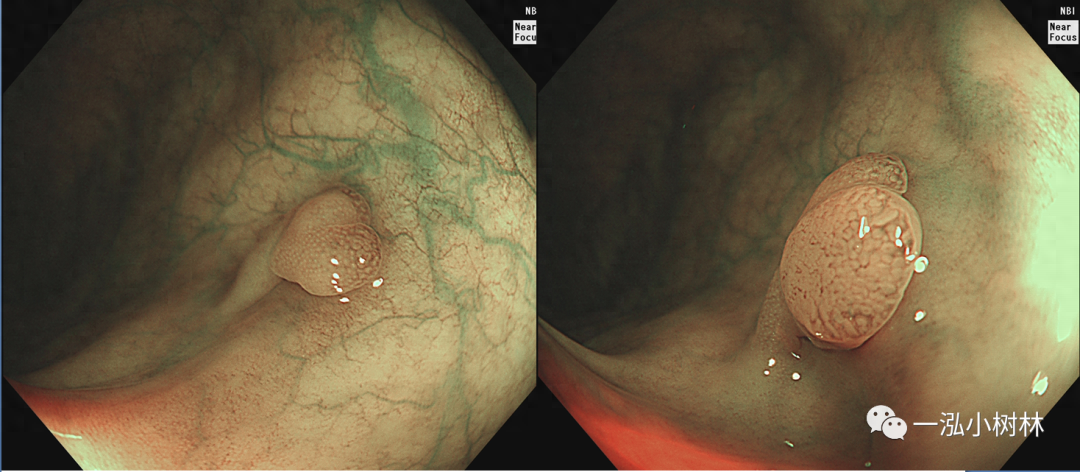

图3 结肠管状腺瘤(Pit Pattern IIIL型)